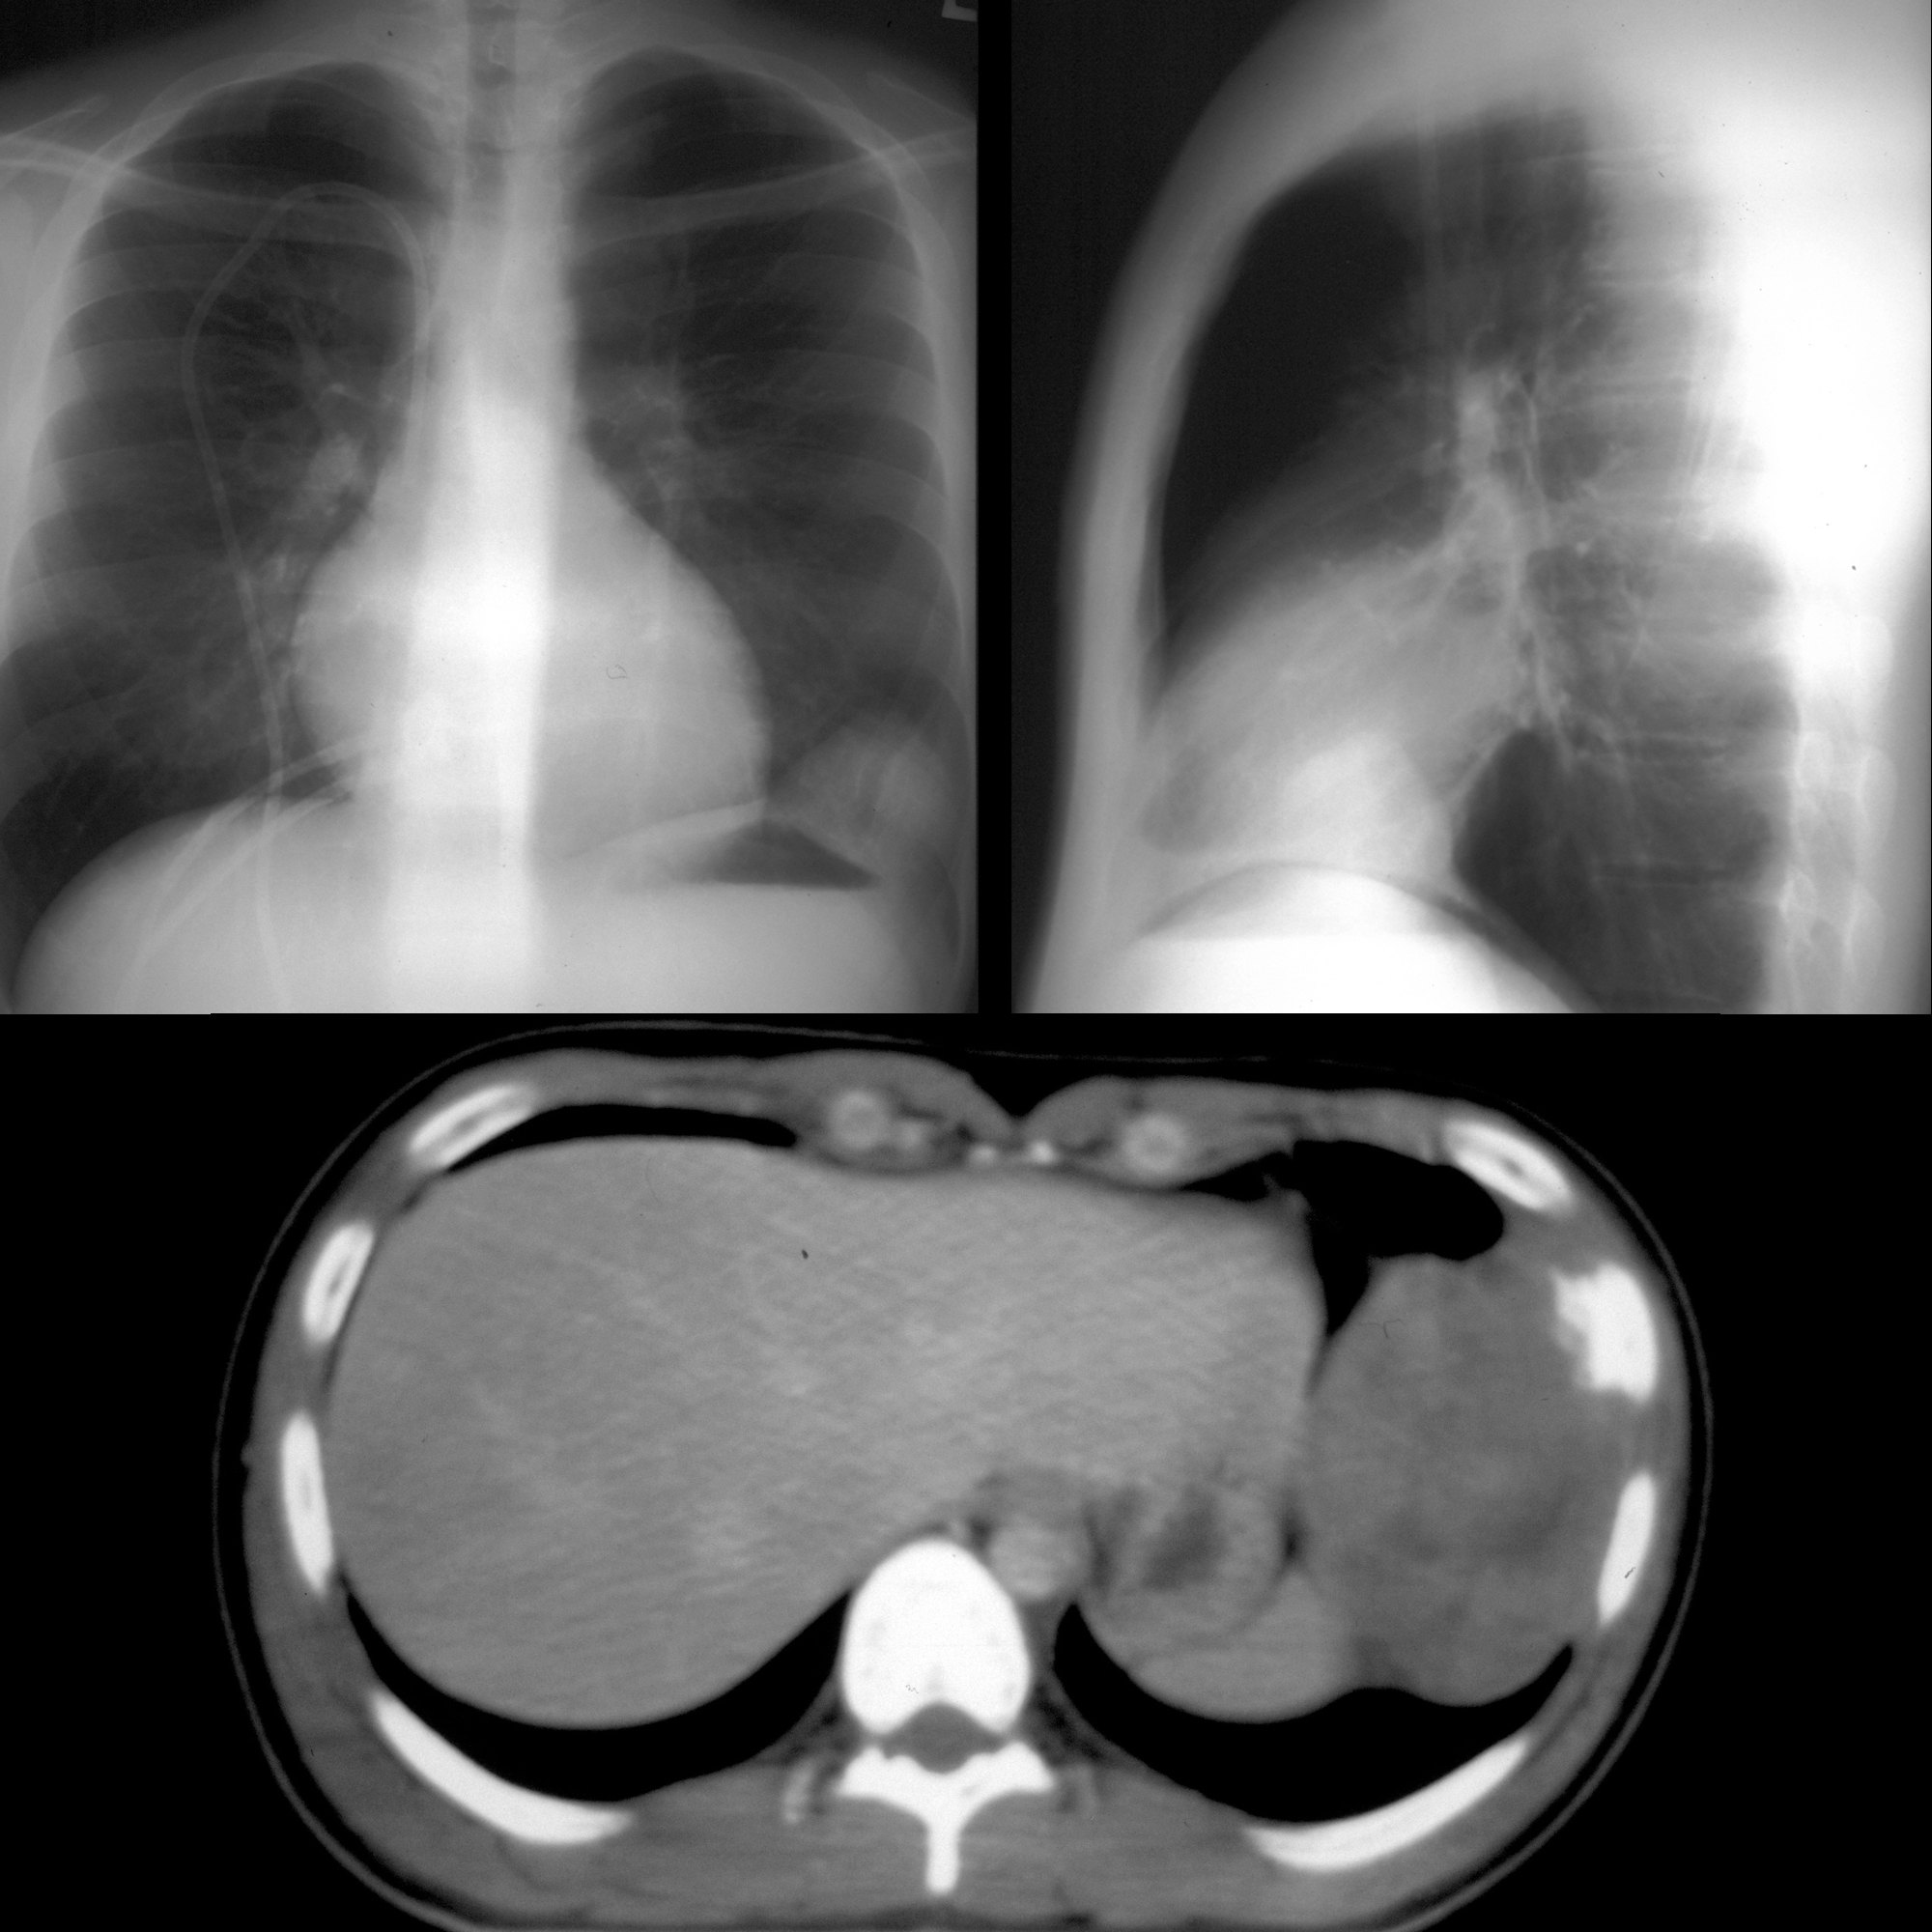

Pediatric Imaging on Twitter "Teen with fever+left pleuritic chest Pleuritic Chest Pain Covid 19 pleurisy is a painful lung condition that makes it hard to breathe. pericarditis should be considered in patients with chest pain, st elevation on ecg, a normal coronary. our patient subsequently developed a fever and shortness of breath and his nasopharyngeal swab performed. Pleuritic Chest Pain Covid 19.

Manual Of Medicine on Twitter "37yearold man presents to the Pleuritic Chest Pain Covid 19 pericarditis should be considered in patients with chest pain, st elevation on ecg, a normal coronary. pleurisy is a painful lung condition that makes it hard to breathe. our patient subsequently developed a fever and shortness of breath and his nasopharyngeal swab performed. Pleuritic Chest Pain Covid 19.